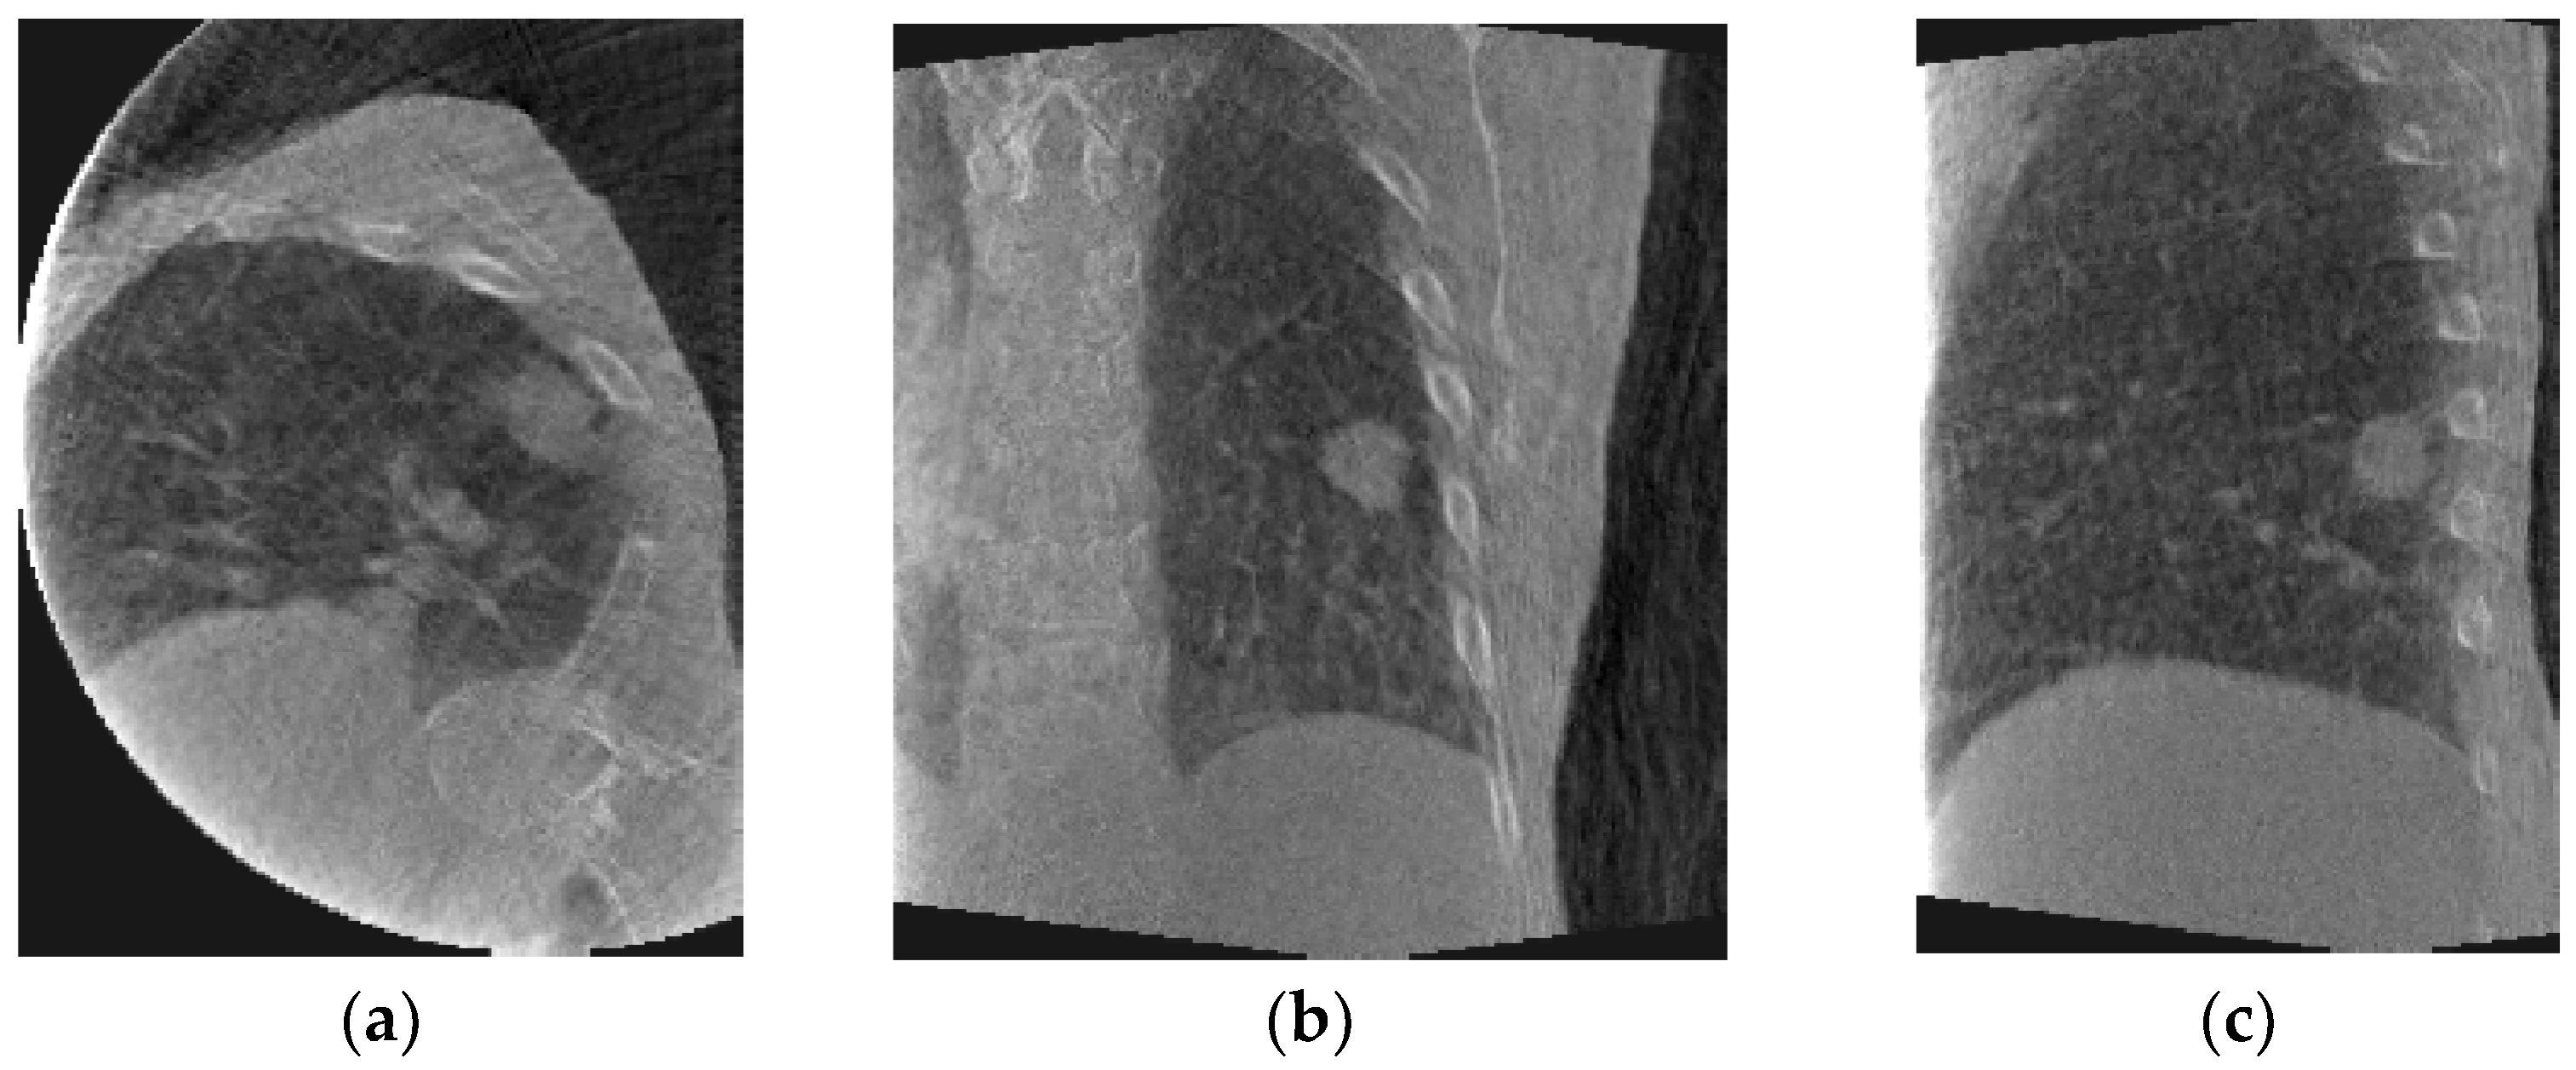

The estimated fluoroscopic 3D images for each of the datasets were evaluated. Figure 5 shows axial, coronal, and sagittal slices of a sample estimated fluoroscopic 3D image from patient #2. Figure 6 shows coronal slices of two estimated fluoroscopic 3D images from patient #2 at different breathing phases. As can be noticed from Figure 6, the estimated fluoroscopic images were able to capture the anatomical motion represented in the CBCT projections used in the optimization module.

Figure 5.

Sample estimated fluoroscopic 3D image from patient #2 dataset: (a) axial, (b) coronal, and (c) sagittal slices.